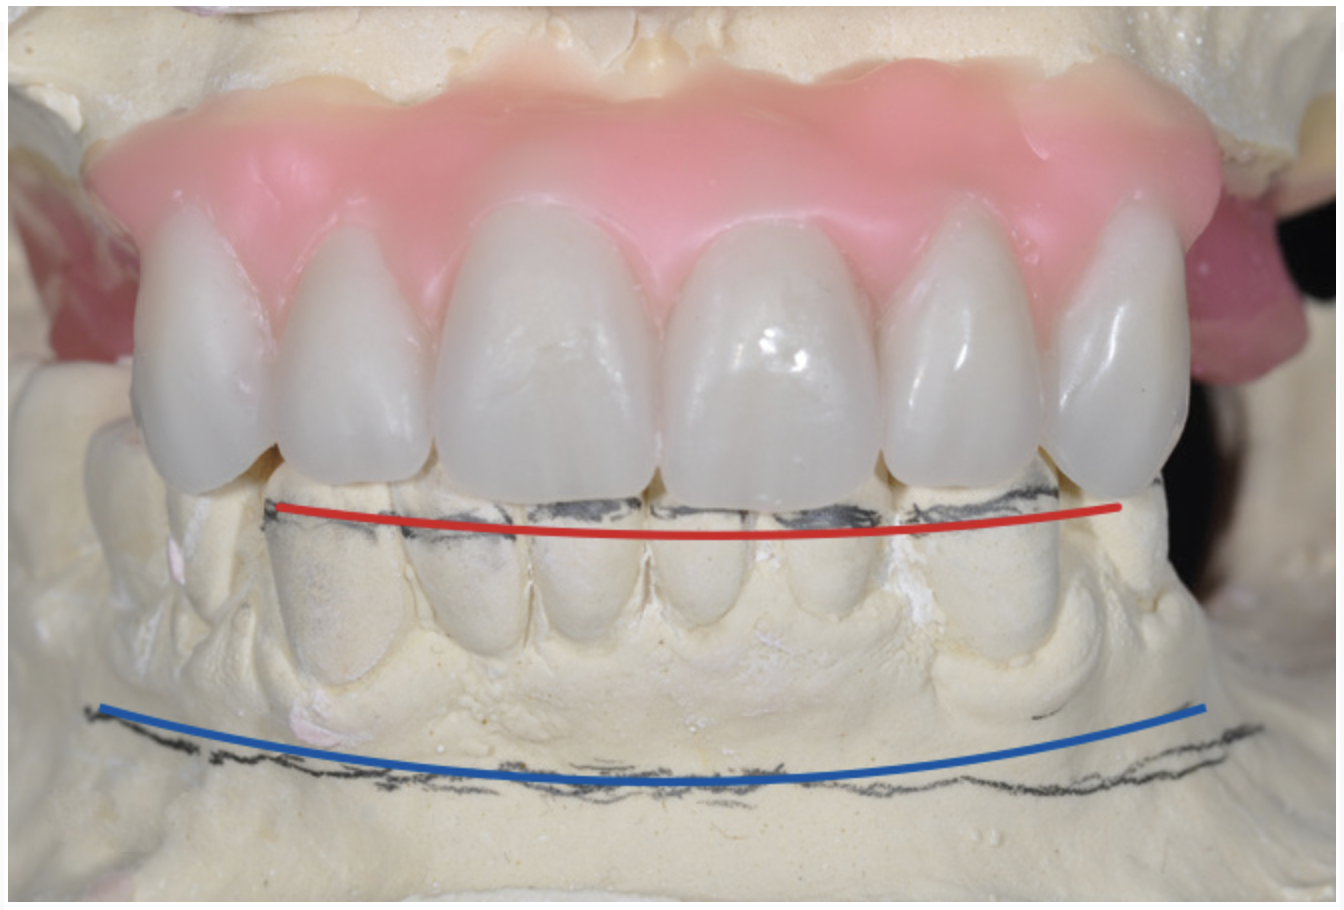

An important advantage of this approach is the ability to simulate bone reduction on the models and verify the presence of 15 mm to 17 mm and 13 mm to 15 mm of required inter-occlusal space for maxillary and mandibular restorations, respectively. This creates a platform for a diagnostic wax-up of the proposed dental rehabilitation and fabrication of wax prosthesis try-ins when necessary. Finally, a modified All-on-4 provisional prosthesis surgical and restorative guide developed by the authors for restoration-driven surgery and simplified restorative procedures is fabricated (Figure 2 through Figure 8).

Fig 4. Diagnostic wax-up performed after model surgery simulating maxillary tooth extraction. Note that inferior repositioning of the incisal plane helped create the 15 mm to 17 mm inter-occlusal space needed for the maxillary All-on-4 provisional restoration.

Figure 4